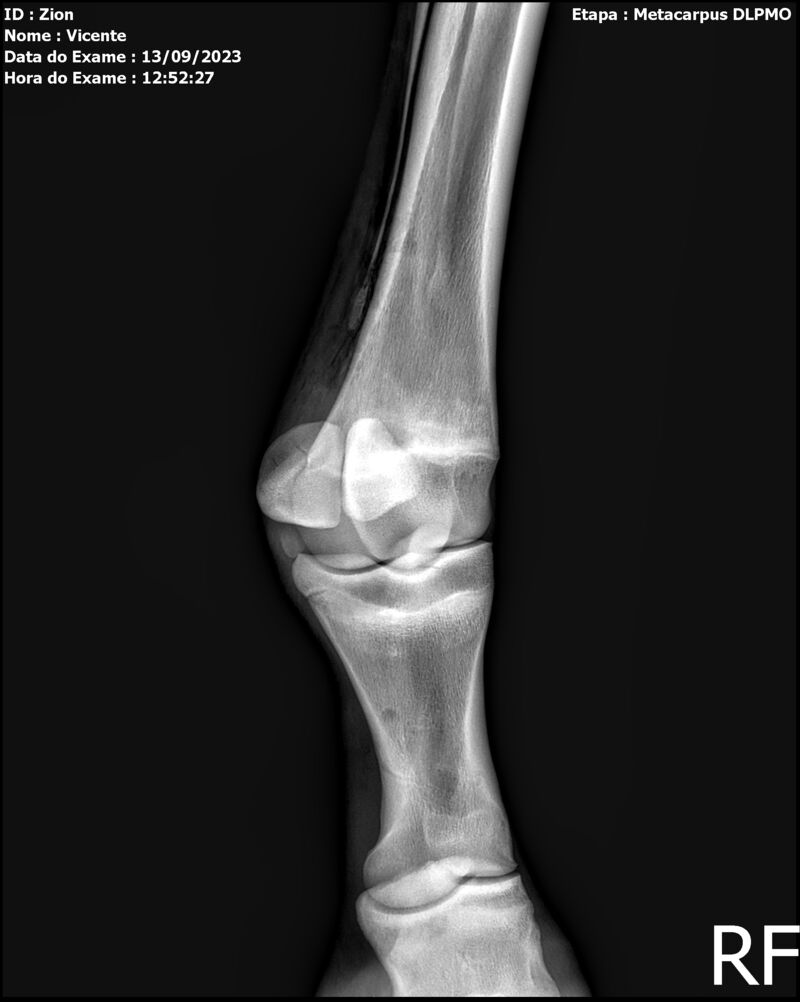

ZION ZC

Raça: BRASILEIRO DE HIPISMO

Sexo: MACHO - POTRO

Nascimento: 17/12/2022

Altura Aproximada: 1,51

Pel.: CASTANHO

Registro: EM AND

Vend.: VICENTE CONTE

Local : PORTO FELIZ/SP